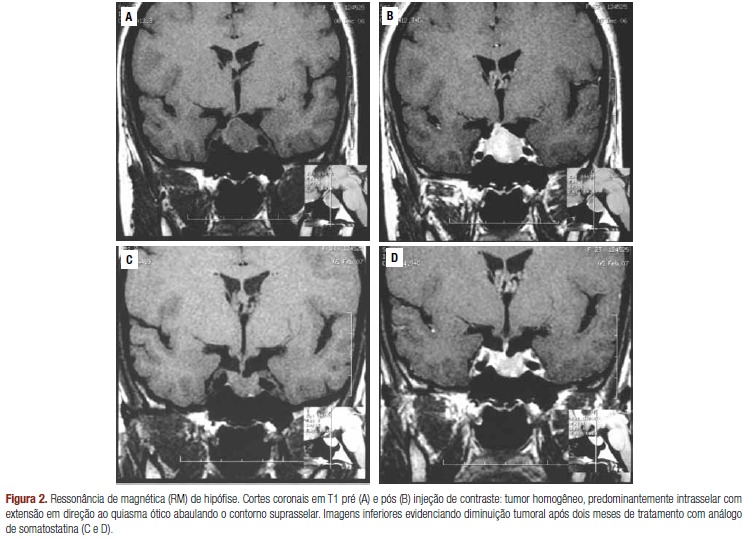

- Hipotireoidismo Central (Secundário e Terciário): É responsável por cerca de 10% dos casos e decorre de uma deficiência na produção de TSH pela hipófise (secundário) ou de TRH pelo hipotálamo (terciário). Tumores hipofisários são uma causa comum. O perfil laboratorial aqui é de T4L baixo com TSH baixo.